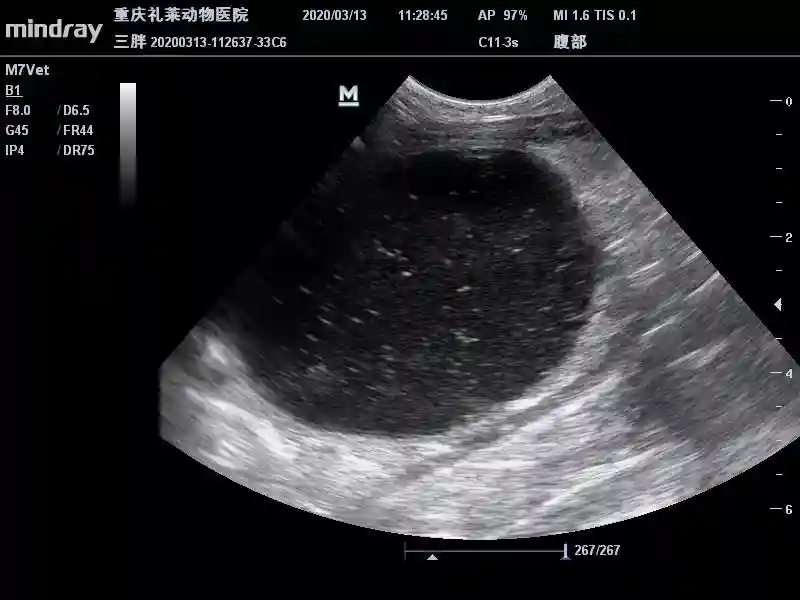

3月13日B超复查

膀胱内呈散在高回声声影。